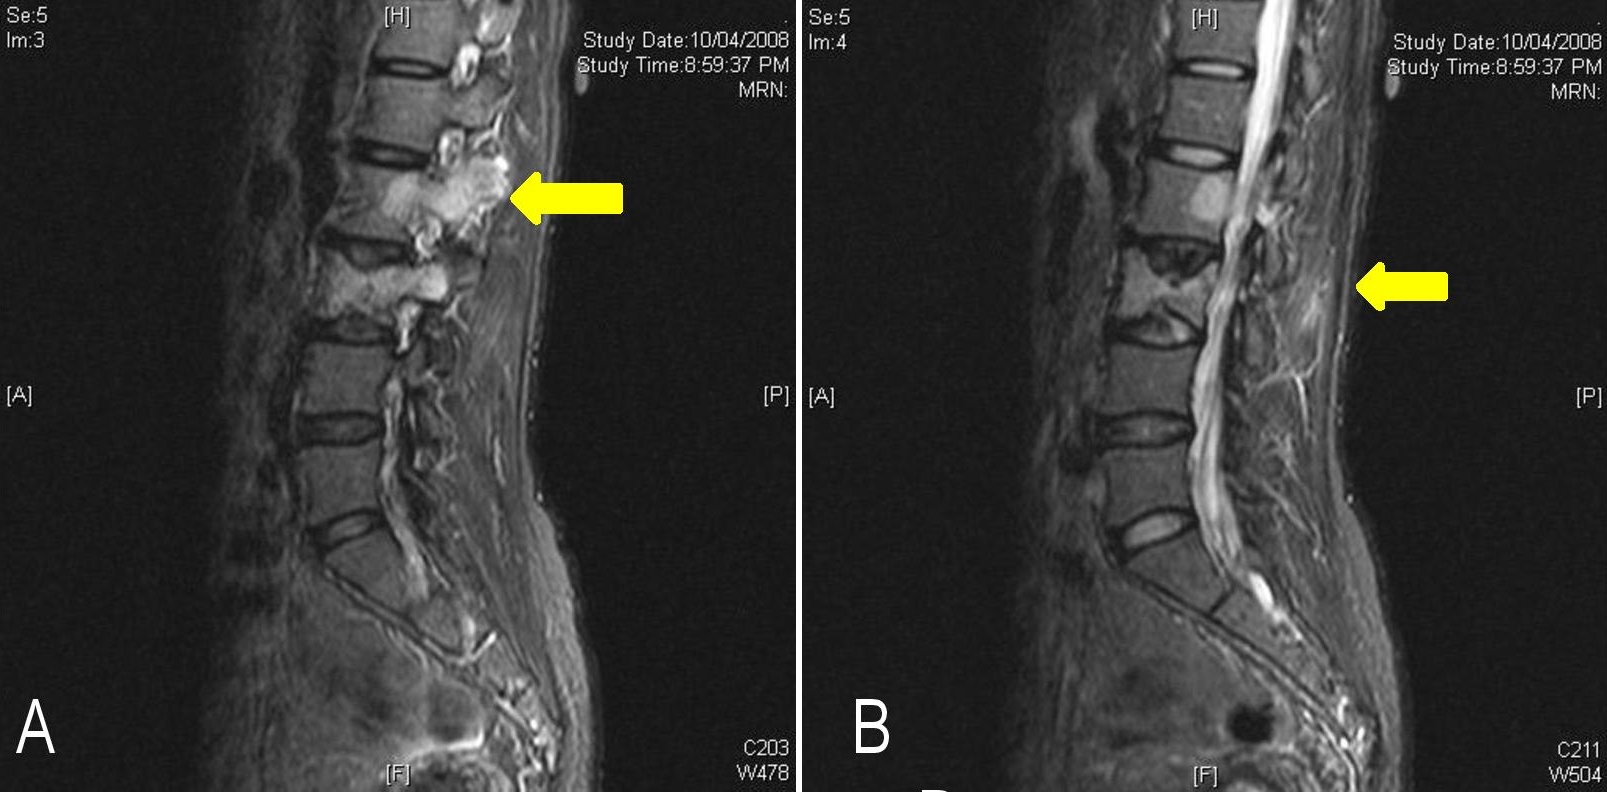

A 46-year old female presented to our hospital in 2008 with gradual onset of paraparesis of both lower limbs. She had right hemi-thyroidectomy performed 12 years ago at another hospital. She did not monitor TSH, nor did she receive levothyroxine replacement at any time. Magnetic resonance imaging (MRI) of the spine showed multiple areas of abnormal marrow signals in the spine, involving the T4, T6, T7, T12, L2, L3 and S1 vertebrae. Collapse of the T4 vertebra was seen with posterior cortical margin convexity and associated pre- and para-spinal and anterior epidural soft tissue components, causing compression on the thecal sac with moderate to severe secondary central canal stenosis (Figures 1A and B). Computed tomography (CT)-guided biopsy of the third lumbar spinal lesion revealed tumor cells which were positive for thyroglobulin immunohistochemistry, suggestive of metastatic follicular thyroid carcinoma.

Figure 1. Magnetic resonance imaging of the spine showing vertebral metastases (yellow arrow) on parasagittal (A) and sagittal (B) views.